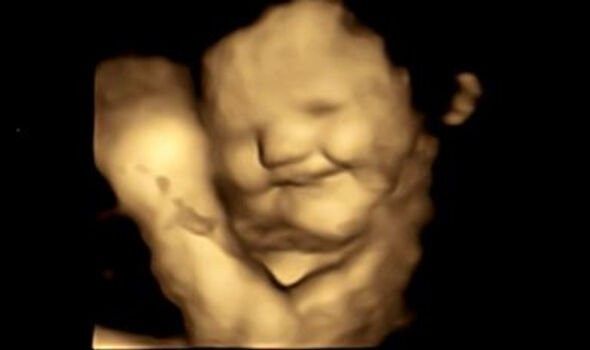

Eating carrots during pregnancy makes babies happy and green cabbage Having Carrots During Pregnancy The fiber in carrots aids in preventing constipation, a common woe during pregnancy, ensuring a healthy digestive system. We now list the top. Properties and benefits of eating carrots during pregnancy: These calories should come from a balanced diet of protein,. Eating carrots during pregnancy is generally considered safe and can even be beneficial for both the mother and the. Having Carrots During Pregnancy.